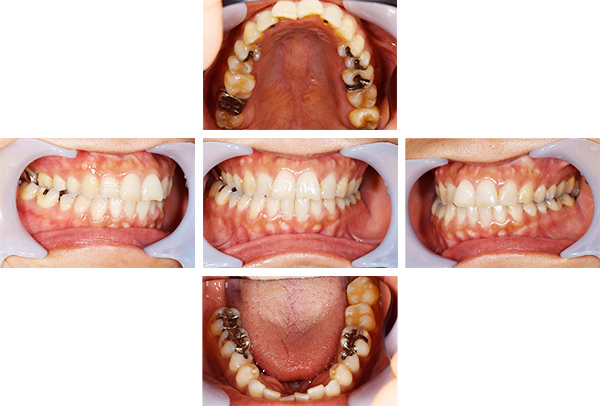

インレー・クラウン・インプラント症例

治療前

治療後

治療期間 16回(8ヶ月)

費用 ・インプラント(FCZ)1本

・セラミックインレー6本

・オールセラミックプレミアムクラウン6本

・FCZ6本

合計:2,552,000円

治療リスク・副作用 ・詰め物、被せ物をする時は自分の歯を削ることになります

・歯ぎしり・食いしばりが強い方は、セラミックが割れてしまうことがあります。